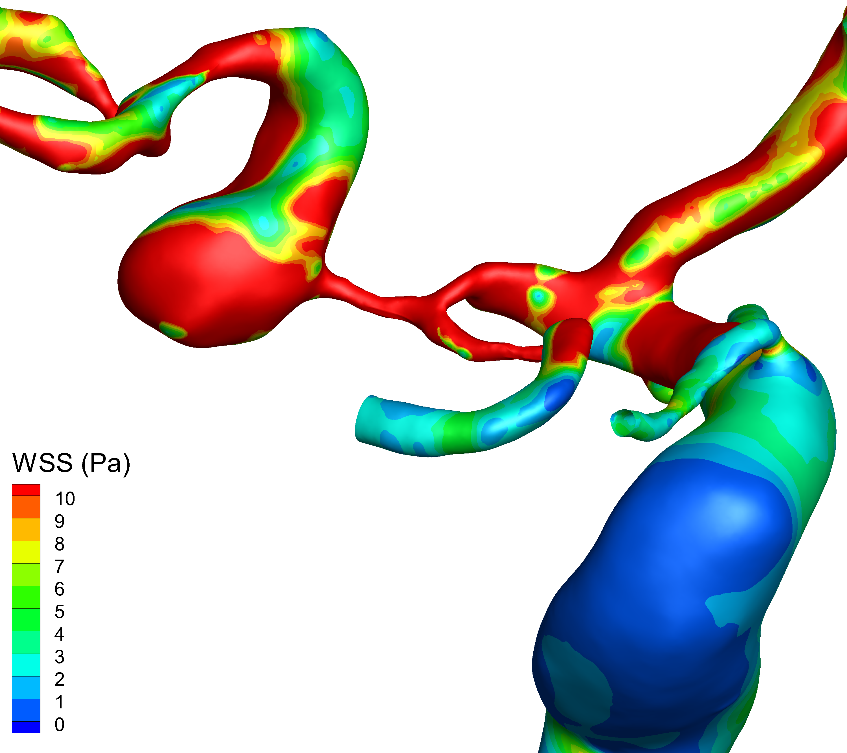

壁面剪切应力

WSS:壁面剪应力,表示血流作用于血管壁而产生的切向作用力。颜⾊越红,血流作用于血管内壁的摩擦力越大。

WSS:wall shear stress

2.可行性:术前完善高分辨磁共振、DSA以及血流动力学,结合患者病情制定合理手术策略;

3.安全性:术前经血流动力学与形态学充分评估动脉瘤应力情况与破裂风险,结合患者病情综合考量选择同期治疗狭窄与动脉瘤;